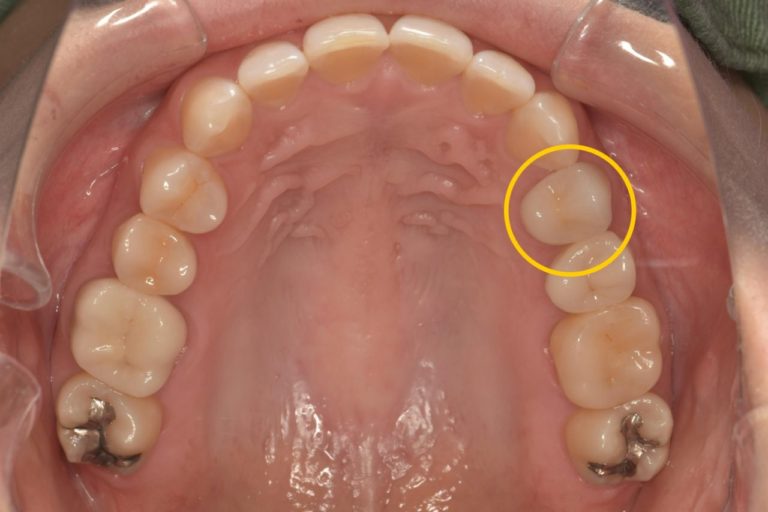

術後

| 年代/性別 | 40代/女性 |

|---|---|

| 症状 | 他院で2ヶ月間根管治療をしているが治らず、歯根端切除術を行う予定。 ただ、骨の吸収が大きく長く持たない可能性があり、抜歯になっても骨の吸収が大きく、インプラントはできない。 と診断された。 |

| 費用 | 初診診断料:¥16,500 感染根管治療:¥154,000 リトリートメント:¥44,000 MTAセメント::¥44,000 ファイバーコア:¥38,500 オールセラミックス:¥187,000 オールセラミックスインレー:¥99,000 歯髄温存療法:¥66,000 |

| 備考 | メリット:将来的に歯を保存出来る デメリット:歯科医師に高い技術が求められる |